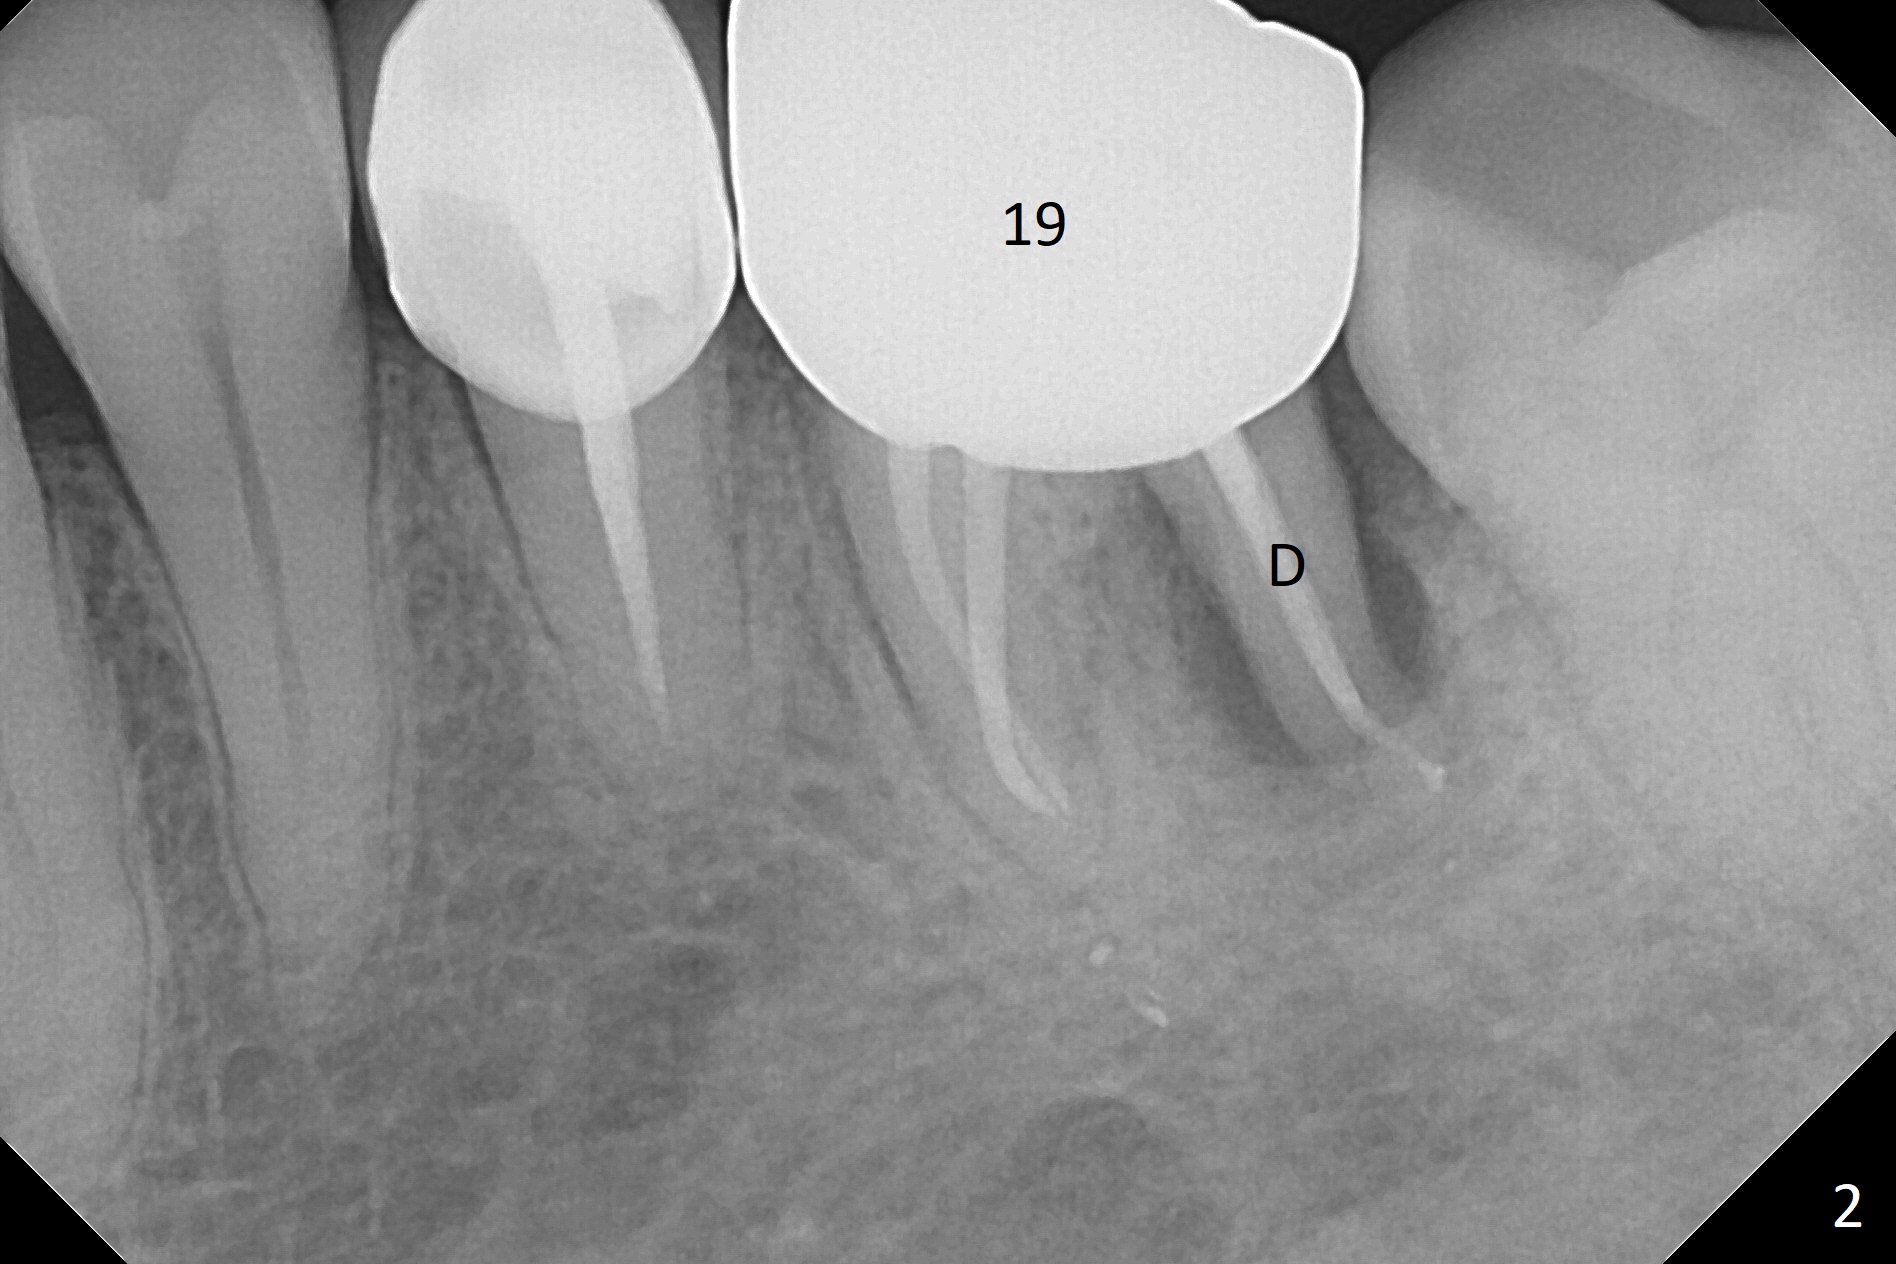

A 54-year-old man has distal (D) root fracture at #19 while the implant at #2 is osteointegrarting (Fig.1,2). Because of the large distal defect (Fig.3, after extraction), osteotomy (red line) will be initiated in the mesial socket (Fig.4, as distal as possible, with the coronal end in the middle of the socket) or the mesial slope of the septum (Fig.5) so that the implant (green) will be supported by the distally displaced septum (Fig.6 arrow). CT taken 8 months later confirms distal root fracture. A 6x11.5 mm or longer implant seems to be appropriate for the site (Fig.7). Three years later there is severe buccal swelling (Fig.8) with vertical mesial and distal root fractures (Fig.9). Although the buccal plate is lost, the septum remains (Fig.10 S), which will provide with blood supply to the bone graft (Fig.11), covered with Bioxclude and 6-month membrane and PSA suture. The bone density in the mesial and distal sockets is higher than that in the septum 8 months post cortical bone graft (Fig.12). In spite of bone graft, the buccolingual width reduces by almost 4 mm 8 months post extraction (Fig.3,4). In spite of bone graft, the buccolingual width reduces by almost 4 mm in 8 months post extraction (Fig.3,4). A 5x11.5 mm implant will be placed (Fig.15).